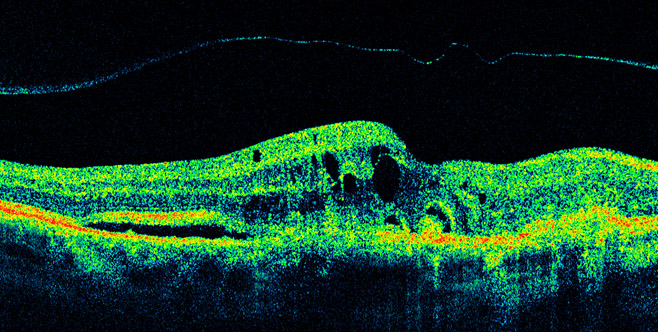

Macular Edema can be caused from a number of ocular diseases such has vein occlusion, ocular inflammation, post surgical complication, diabetes, hypertension, and many other diseases. What most people will notice is a gradual or even sometimes, sudden changes in vision that does not improve. Essentially the retina becomes filled with fluid that causes it to become irregular in shape, thus losing the ability to detect light evenly. Devices such as the OCT, as shown in the picture, can easily detect macular edema that sometimes can be missed by the naked eye.